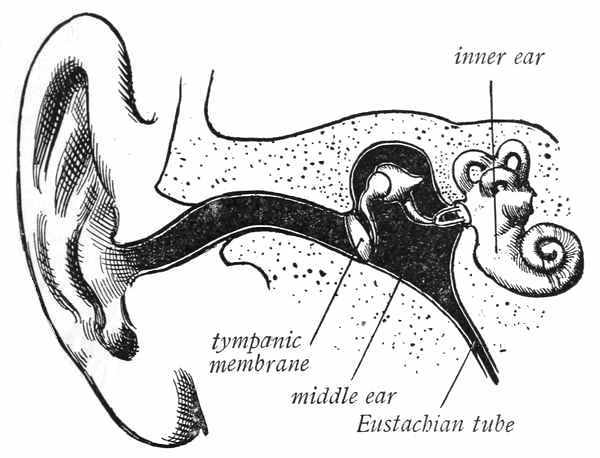

Sometimes children are backward in their school work because they cannot hear well. Your teacher can test your hearing by holding a watch near your ear. If you cannot hear a watch tick when it is held six feet from your ear, ask your father to take you to your doctor, that he may treat your ears.

If your hearing is perfect, the best way to take care of the ears is to let them alone. Never try to dig into the canal that leads to the middle ear. The ears must of course be washed to keep them clean, but in washing the ear you should not touch the delicate canal leading to the drum. A great specialist once said, "Never put anything smaller than your elbow into your ear," to which another great[59] specialist added, "And wrap a towel around your elbow." Never try to dig the wax out of your ears; it belongs in your ears; it is there for a purpose, so let it alone. If it becomes hardened, you cannot get it out and will only injure your ears in trying to do so. An ear spoon is a dangerous thing.